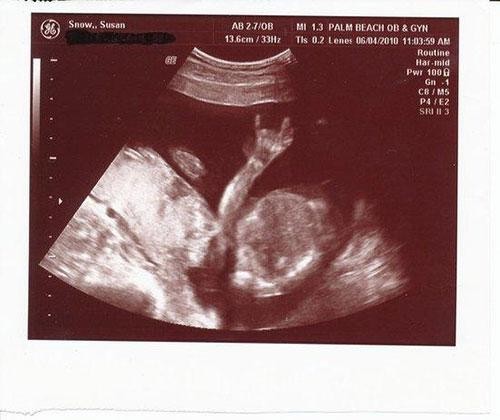

Şimdi de ultrasonda bebek yerine bir ördek gördüğünüzü düşünün. Merak etmeyin, aslında sadece “pareidolia” sendromunu yaşıyorsunuz.

İşte bebek ultrasonlarında çekilen ve bazı anne babalara mini kalp krizi geçirten bebek fotoğrafları!